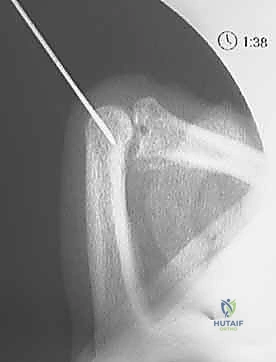

2. K-wire Placement: The Dorsal Blocking Pin

Once you have a stable, concentrically reduced joint, we proceed with placing the K-wire. The principle here is to insert a K-wire into the proximal phalanx, creating a mechanical block that prevents the middle phalanx from hyperextending and re-dislocating dorsally, while still allowing full flexion.

• Choose Your Wire: We'll use a smooth K-wire, typically 0.035-inch or 0.045-inch in diameter. The smaller diameter is often preferred in the digits to minimize bone removal and potential for articular damage, but a 0.045-inch wire offers more rigidity.

• Joint Positioning: Maintain the PIP joint in 90 degrees or more of flexion. This is absolutely critical. Hyperflexion of the joint serves two purposes:

1. It ensures the extensor mechanism (central slip) is relaxed and displaced dorsally, minimizing the risk of tethering it with the K-wire.

2. It positions the proximal phalanx head optimally for pin insertion, allowing the pin to pass through the dorsal aspect without entering the articular surface.

• Entry Point Selection: Identify the distal, dorsal aspect of the proximal phalanx. The ideal entry point is just proximal to the PIP joint line, slightly off-center (either radially or ulnarly) to avoid the central slip of the extensor tendon. If you place it centrally, you risk tethering the extensor mechanism, which can limit future joint flexion.

• Palpation: Palpate the dorsal aspect of the proximal phalanx head. You want to enter the bone just proximal to the articular cartilage.

• Skin Incision: A small stab incision with an 11-blade scalpel can facilitate K-wire entry and prevent skin tenting.

Image

Clinical view of K-wire entry point.

* K-wire Insertion Angle: Insert the K-wire percutaneously, aiming in a retrograde direction, approximately 30 degrees off the long axis of the proximal phalanx. The angle is crucial to ensure the pin is within the bone and not crossing the joint.

* Fluoroscopic Guidance (Constant Monitoring):

* Initial Entry: Advance the K-wire slowly with a power drill or by hand. Confirm its entry into the bone of the proximal phalanx on both AP and lateral fluoroscopic views.

* Guidance through Shaft: Guide the wire through the shaft of the proximal phalanx, aiming slightly volar.

* Target Depth: Advance the K-wire until its tip lies just proximal to the articular cartilage of the proximal phalanx head. The tip should not enter the joint space. This is your blocking point.

Fluoroscopic view of K-wire in proximal phalanx (AP).